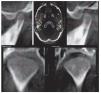

Reconstrucción secundariaEn un segundo proceso de cálculo se pueden obtener más planos de corte a partir de las tomografías axiales obtenidas en la reconstrucción primaria. Entre los métodos principales de reconstrucción secundaria cabe mencionar en primer lugar la reconstrucción multiplanar, que en general debería ser capaz de generar y representar automáticamente cualquiera de los sistemas de software modernos utilizados para el procesamiento de los datos. Normalmente se representan los planos sagital y coronal, que son perpendiculares al corte axial (fig. 11). No obstante, también se pueden obtener reconstrucciones mucho más complejas a partir de una ruta creada de forma manual en el conjunto de datos, por ejemplo7. De este modo, el médico tiene la posibilidad de generar, a partir de un conjunto de datos volumétricos y en muy poco tiempo, una reconstrucción panorámica específica del paciente de estudio o tal vez secciones transversales de la ATM en un plano generado de forma individualizada (fig. 12). En determinados casos esto puede proporcionar mucha más información al médico que la radiografía convencional de la ATM y facilitar de ese modo el diagnóstico y el plan de tratamiento.

Figura 12. Cortes de la ATM del paciente creados manualmente.